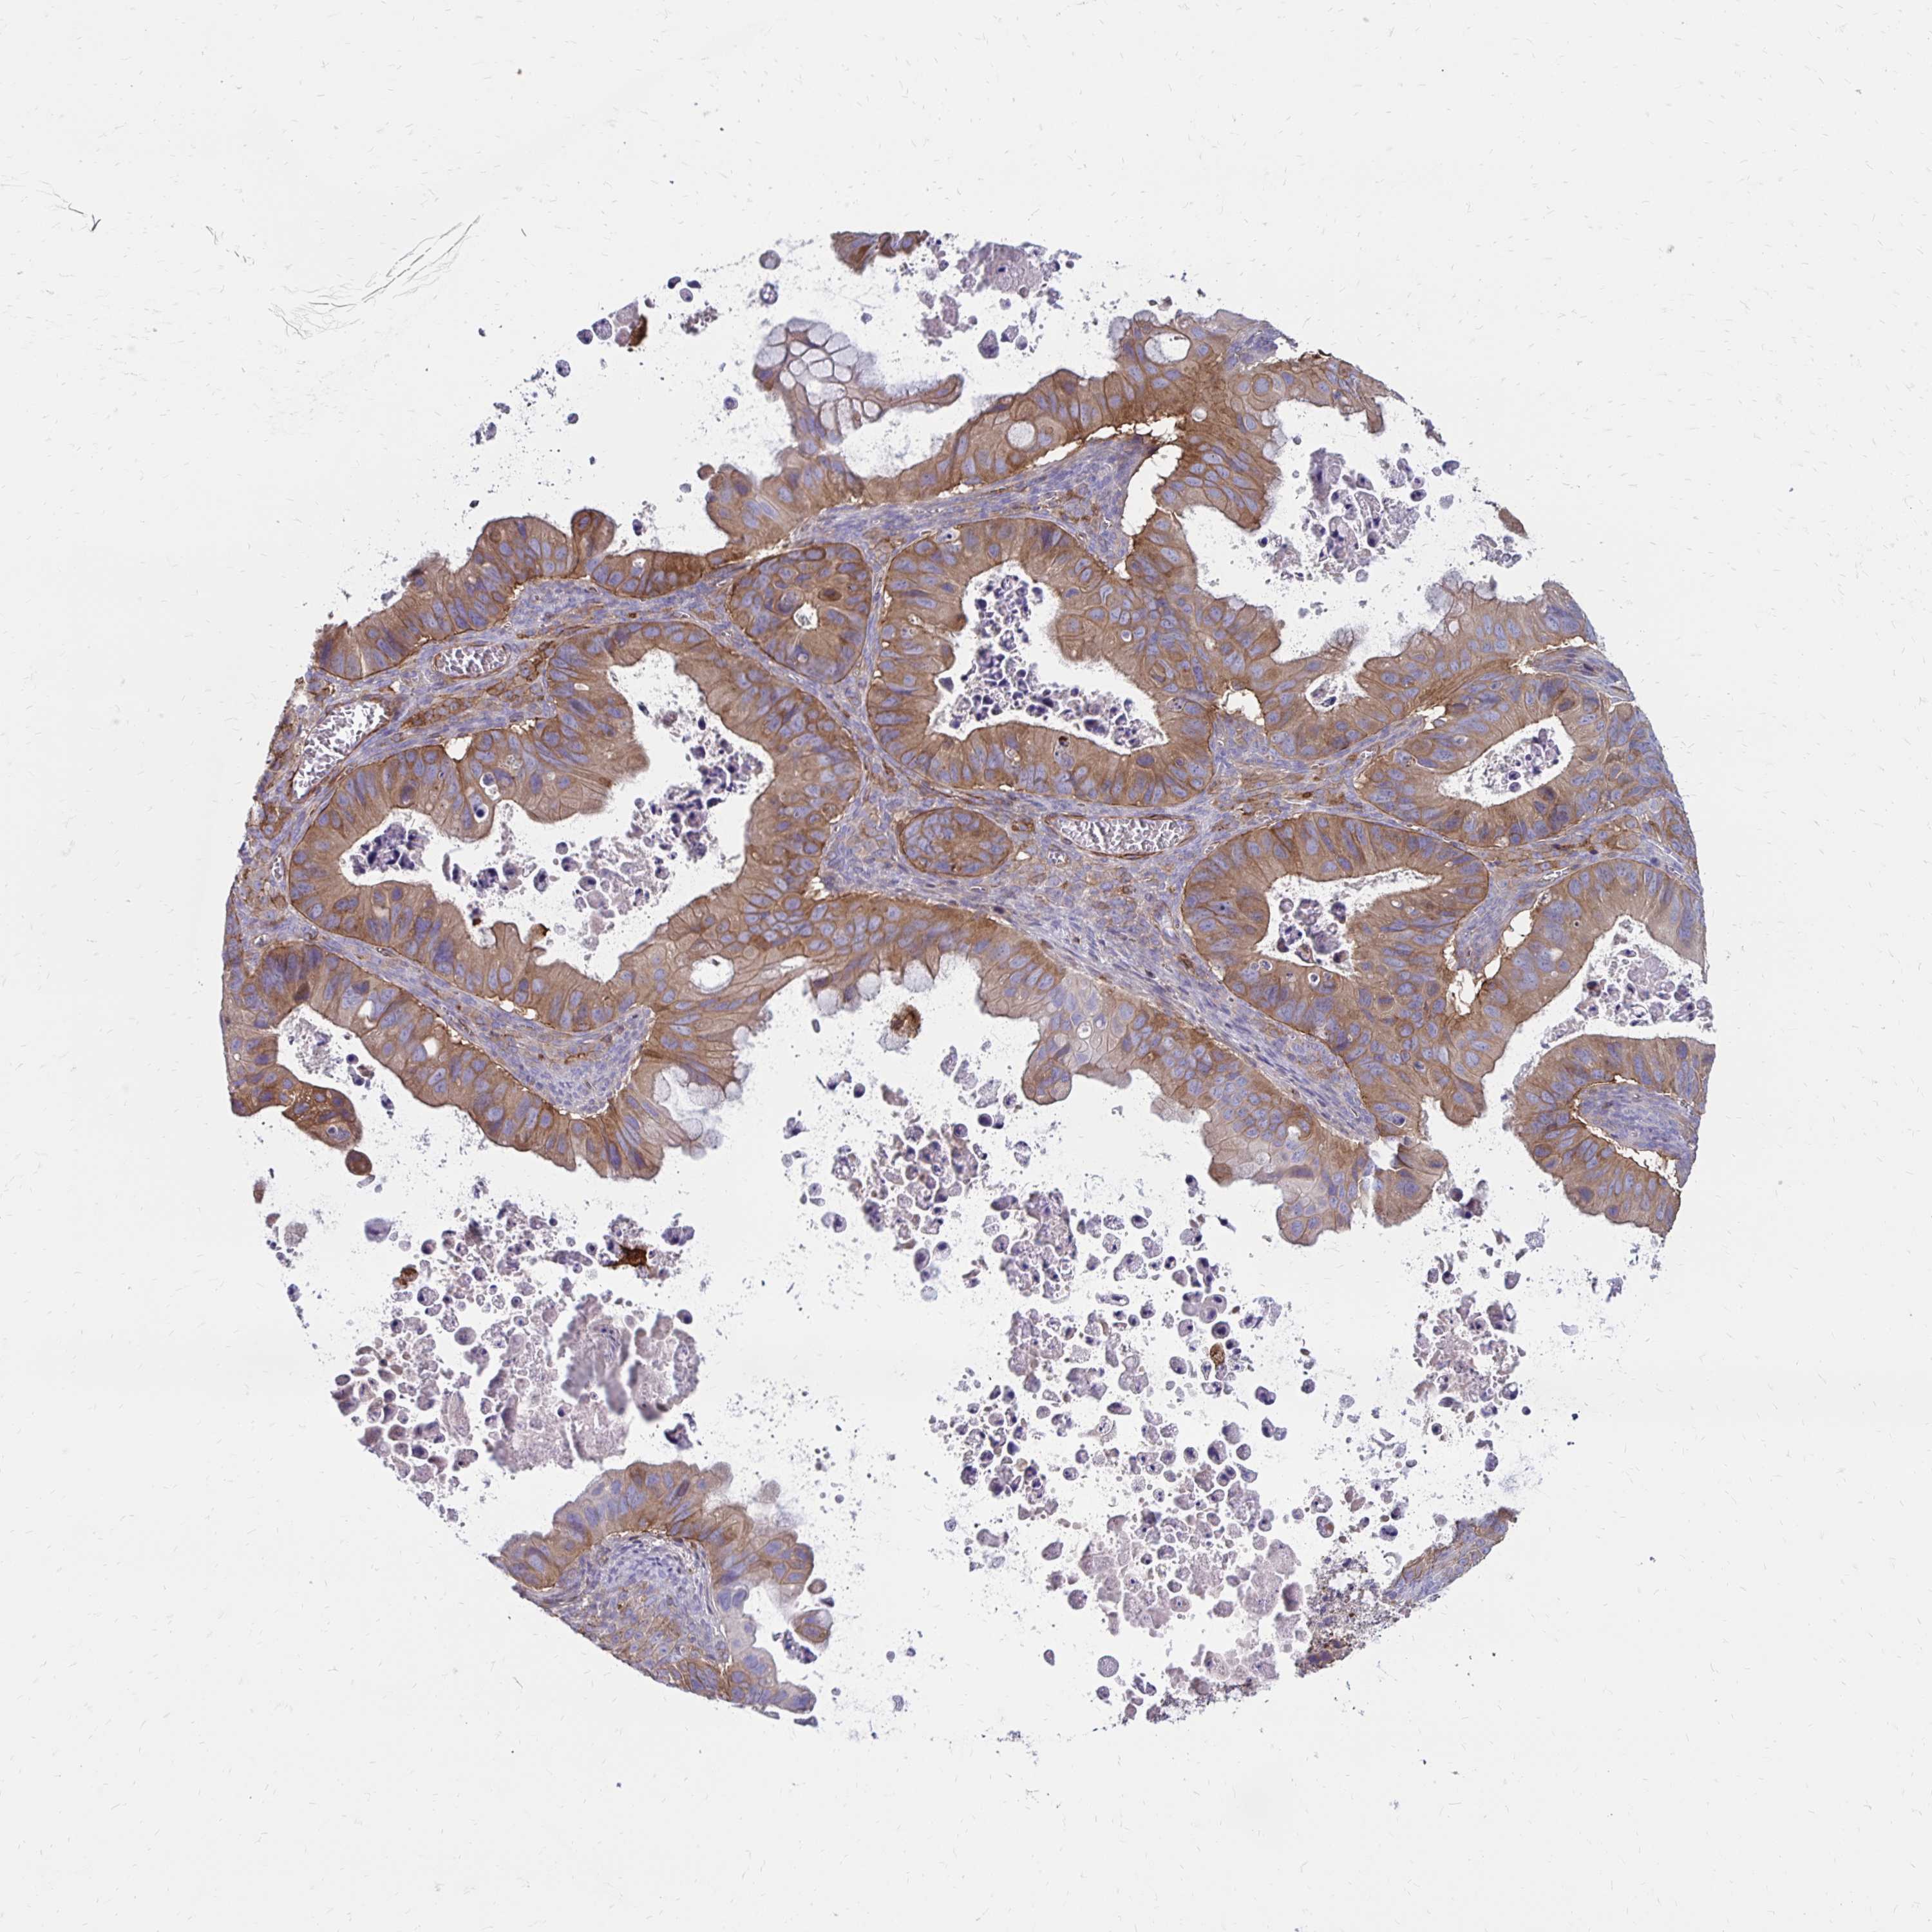

OVARIAN CANCER - Protein expressioni

A mouse-over function shows sample information and annotation data. Click on an image to view it in a full screen mode. Samples can be filtered based on level of antibody staining by selecting one or several of the following categories: high, medium, low and not detected. The assay and annotation is described here.

Note that samples used for immunohistochemistry by the Human Protein Atlas do not correspond to samples in the TCGA dataset.

Antibody stainingi

Antibody staining in the annotated cell types in the current human tissue is reported as not detected, low, medium, or high, based on conventional immunohistochemistry profiling in selected tissues. This score is based on the combination of the staining intensity and fraction of stained cells.

Each image is clickable and will lead to virtual microscopy that enables deeper exploration of all samples and also displays staining intensity scores, fraction scores and subcellular localization as well as patient and tissue information for each sample.

Antibody HPA055338

Antibody HPA056015

Staining

High

Medium

Low

Not detected

Intensity

Strong

Moderate

Weak

Negative

Quantity

>75%

75%-25%

<25%

None

Location

Nuclear

Cytoplasmic/membranous

Cytoplasmic/membranous,nuclear

Cystadenocarcinoma, serous, NOS

Cystadenocarcinoma, mucinous, NOS

Carcinoma, endometroid